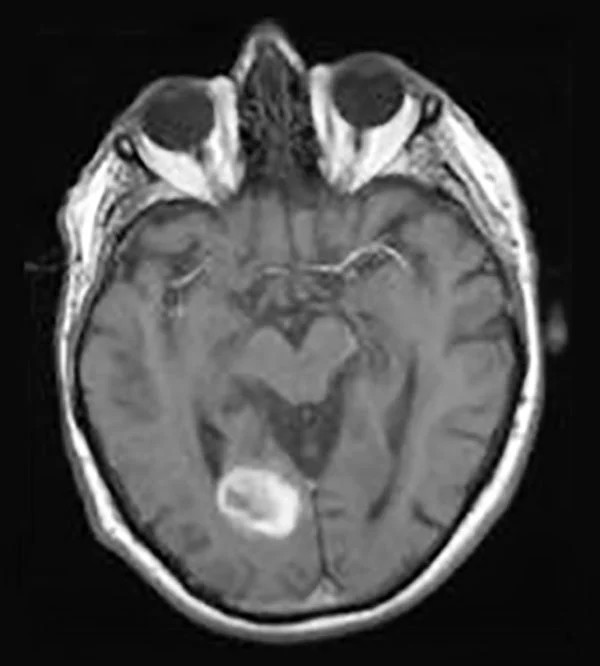

Image credit: Alexis Kocken